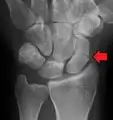

A subtle scaphoid fracture

A more obvious scaphoid fracture on a scaphoid view X ray

Radiolucency around a 12 days old scaphoid fracture that was initially barely visible.[12]